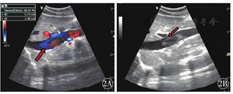

患者1女性,35岁。因"反复双下肢浮肿3个月"于2018年10月19日入院。入院后于2018年10月23日行彩色多普勒超声检查提示下腔静脉近段血流充盈缺损,管腔内为不规则、实质性、混合回声填充并黏附管腔后壁,狭窄率为60%~70%,长约3.0 cm,血栓基底部未见明显血流进入(图1)。右肾静脉无血流信号显示。2018年10月29日复查彩超检查显示下腔静脉近段管腔内混合回声团块上端漂浮,血流冲击基底部,基底部黏附于下腔静脉后壁,血流充盈缺损,狭窄率50%~60%,狭窄段长约3.0~4.0 cm,右肾静脉血流通畅(图2)。为防止血栓脱落导致肺栓塞,于2018年10月30日行下腔静脉滤器置入术,术后患者病情稳定并进一步行下腔静脉置管溶栓术。彩超检查提示下腔静脉内可见溶栓导管,管腔内仍可见不规则、实质性、混合回声填充,血流不规则充盈缺损。混合回声团块上端未见明显漂浮,无明显血流信号进入基底部(图3)。置管溶栓过程中,下腔静脉内仍可见部分附壁血栓黏附,于2018年11月19日行下腔静脉切开取栓、滤器取出术,术中见滤器有小块血栓附着,夹出下腔静脉壁上血栓,部分血栓与下腔静脉后壁黏附紧密,仔细剥离至取栓满意。术后患者生命体征平稳。术后病理诊断:下腔静脉混合血栓。行彩超检查提示下腔静脉内血流通畅,充盈良好,双肾静脉血流通畅(图4)。患者于2019年12月1日出院。